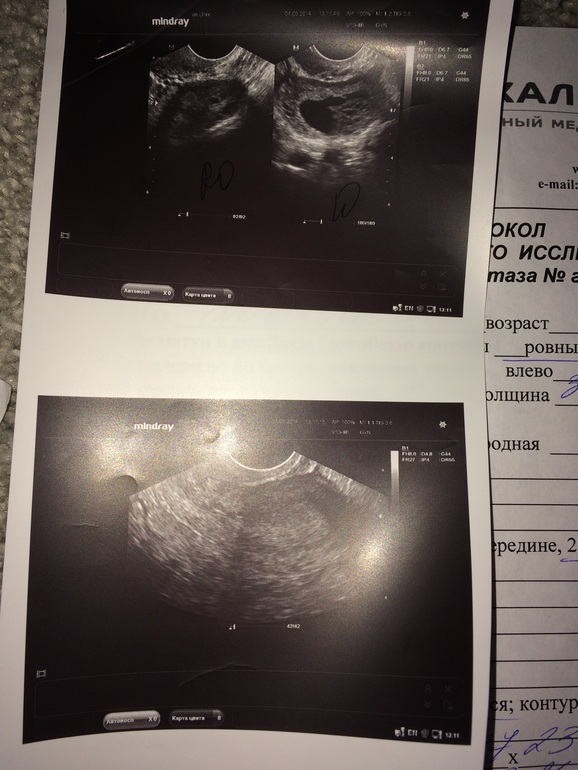

Я посмотрела свои показатели- длинна 45мм, толщина 31, ширина 42. Я посмотрела показатели у меня почти в пределах нормы. Просто интересно стало, может кто разбирается и знает что это и как расценивать значения. Стоит ли мне волноваться?

P.s. Может разберёте что узистка написала

В правом- фолликулы диаметром до 6 мм.

В левом- какое то кистозное образование с какими то компонентами диаметр 26мм.

Кистозно измененный левый яичник.